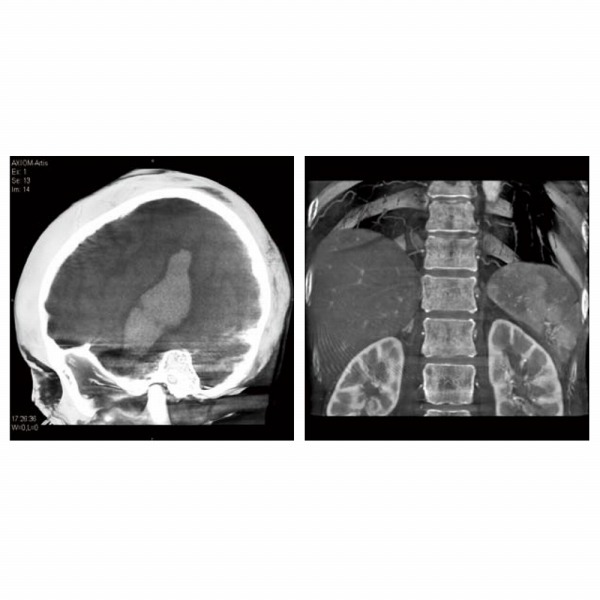

最適なIVR環境を創造するための「プレミアム」システム、それがArtis zee FA PUREです。3Dを「イメージング」から「ガイディングツール」へと進化させる次世代の3Dプラットフォーム、広い視野とアクセス性を両立させたデジタルテクノロジーの結晶「大視野長方形フルフィールドFD」、全身の3Dイメージングを実現し、効率的なスペースを生み出すピボット方式Cアームの有機的な動き、広い可動範囲、そして高いイメージクオリティ。数々の最先端のテクノロジー群を融合し、洗練し、ひとつの有機的なシステムへと昇華して、その先にある「プレミアム」という新たな価値を生み出します。